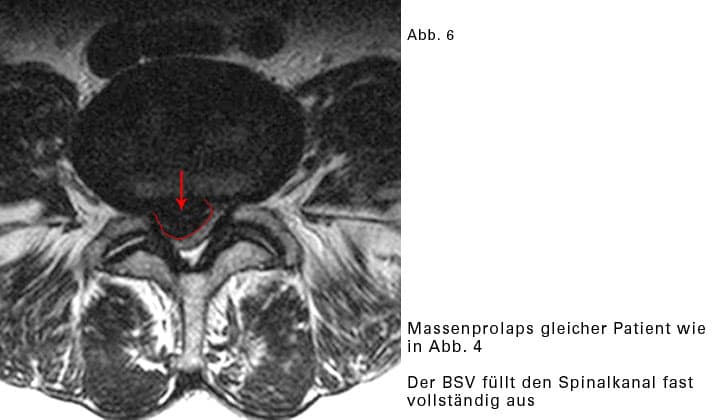

Massenprolaps:

Wenn sehr viel Material des Gallertkernes austritt, wird der BSV Massenprolaps genannt. Dadurch wird im Wirbelkanal sehr viel Platz beansprucht. Es wird sehr eng für sämtliche Nervenwurzeln, die an dieser Stelle vorbeiziehen. Mehrere Nervenwurzeln können gleichzeitig gequetscht werden. Das Beschwerdebild ist entsprechend vielschichtig. Glücklicherweise kommen Massenvorfälle selten vor.